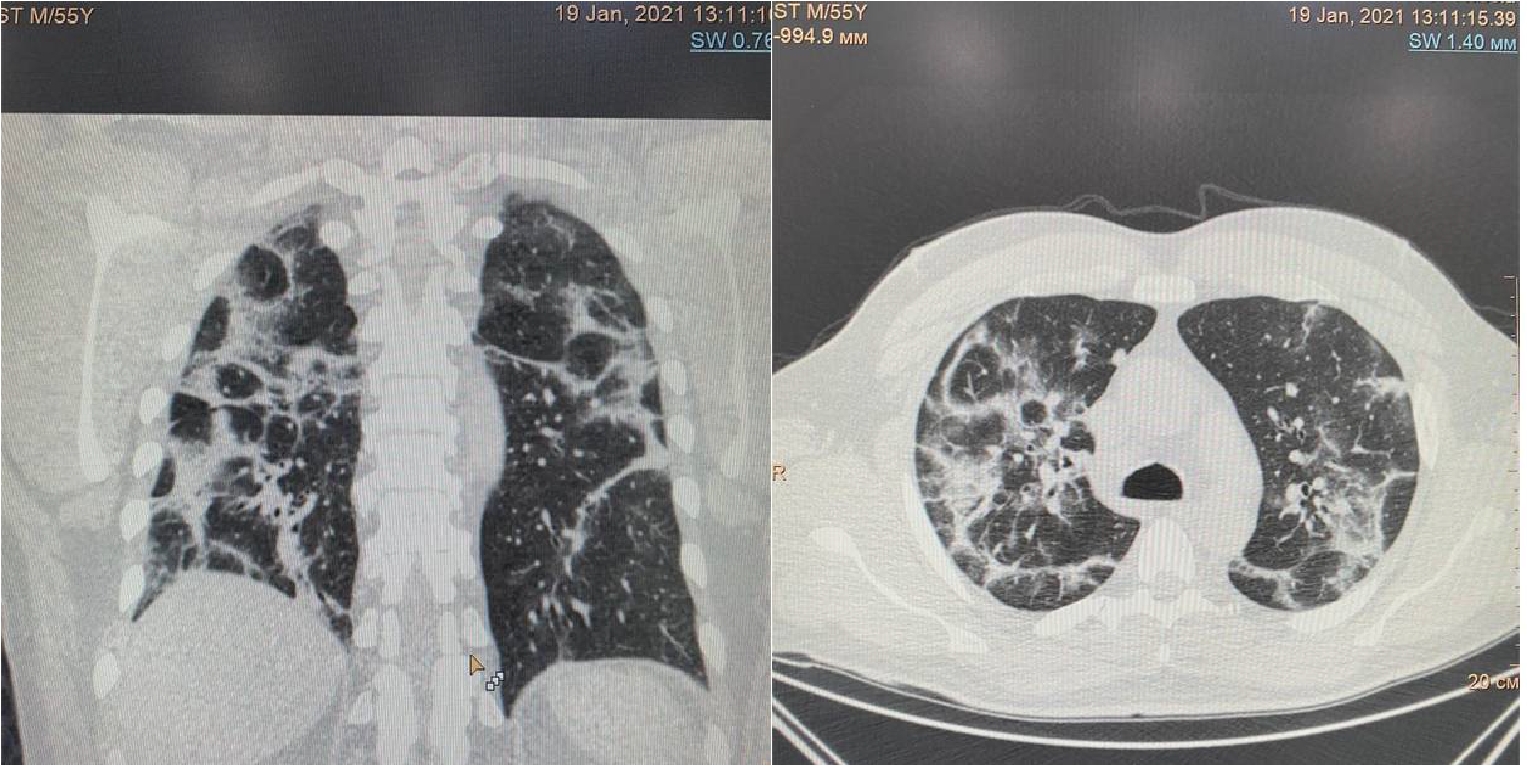

Рисунок 1. МСКТ органов грудной клетки – признаки двусторонней полисегментарной интерстициальной пневмонии (объем поражения 20%, КТ-1).

Пациент (мужчина) 55 лет поступил в стационар с жалобами на сухой кашель, нарушения обоняния и вкуса, одышку при нагрузке, ощущение тяжести в грудной клетке, слабость, боли в мышцах и повышение температуры тела до 380 С. Больной обратился за медицинской помощью на 5 сутки после появления симптомов ОРЗ в связи с неэффективностью самостоятельного лечения и появлением одышки. При поступлении по данным МСКТ легких – признаки двусторонней полисегментарной интерстициальной пневмонии с объемом изменений в пределах 20%, КТ-1 (рис.1). Короновирусная инфекция была подтверждена результатами ПЦР. При поступлении состояние было расценено как средне-тяжелое.